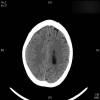

AVC amplio de territorio de A. cerebral media